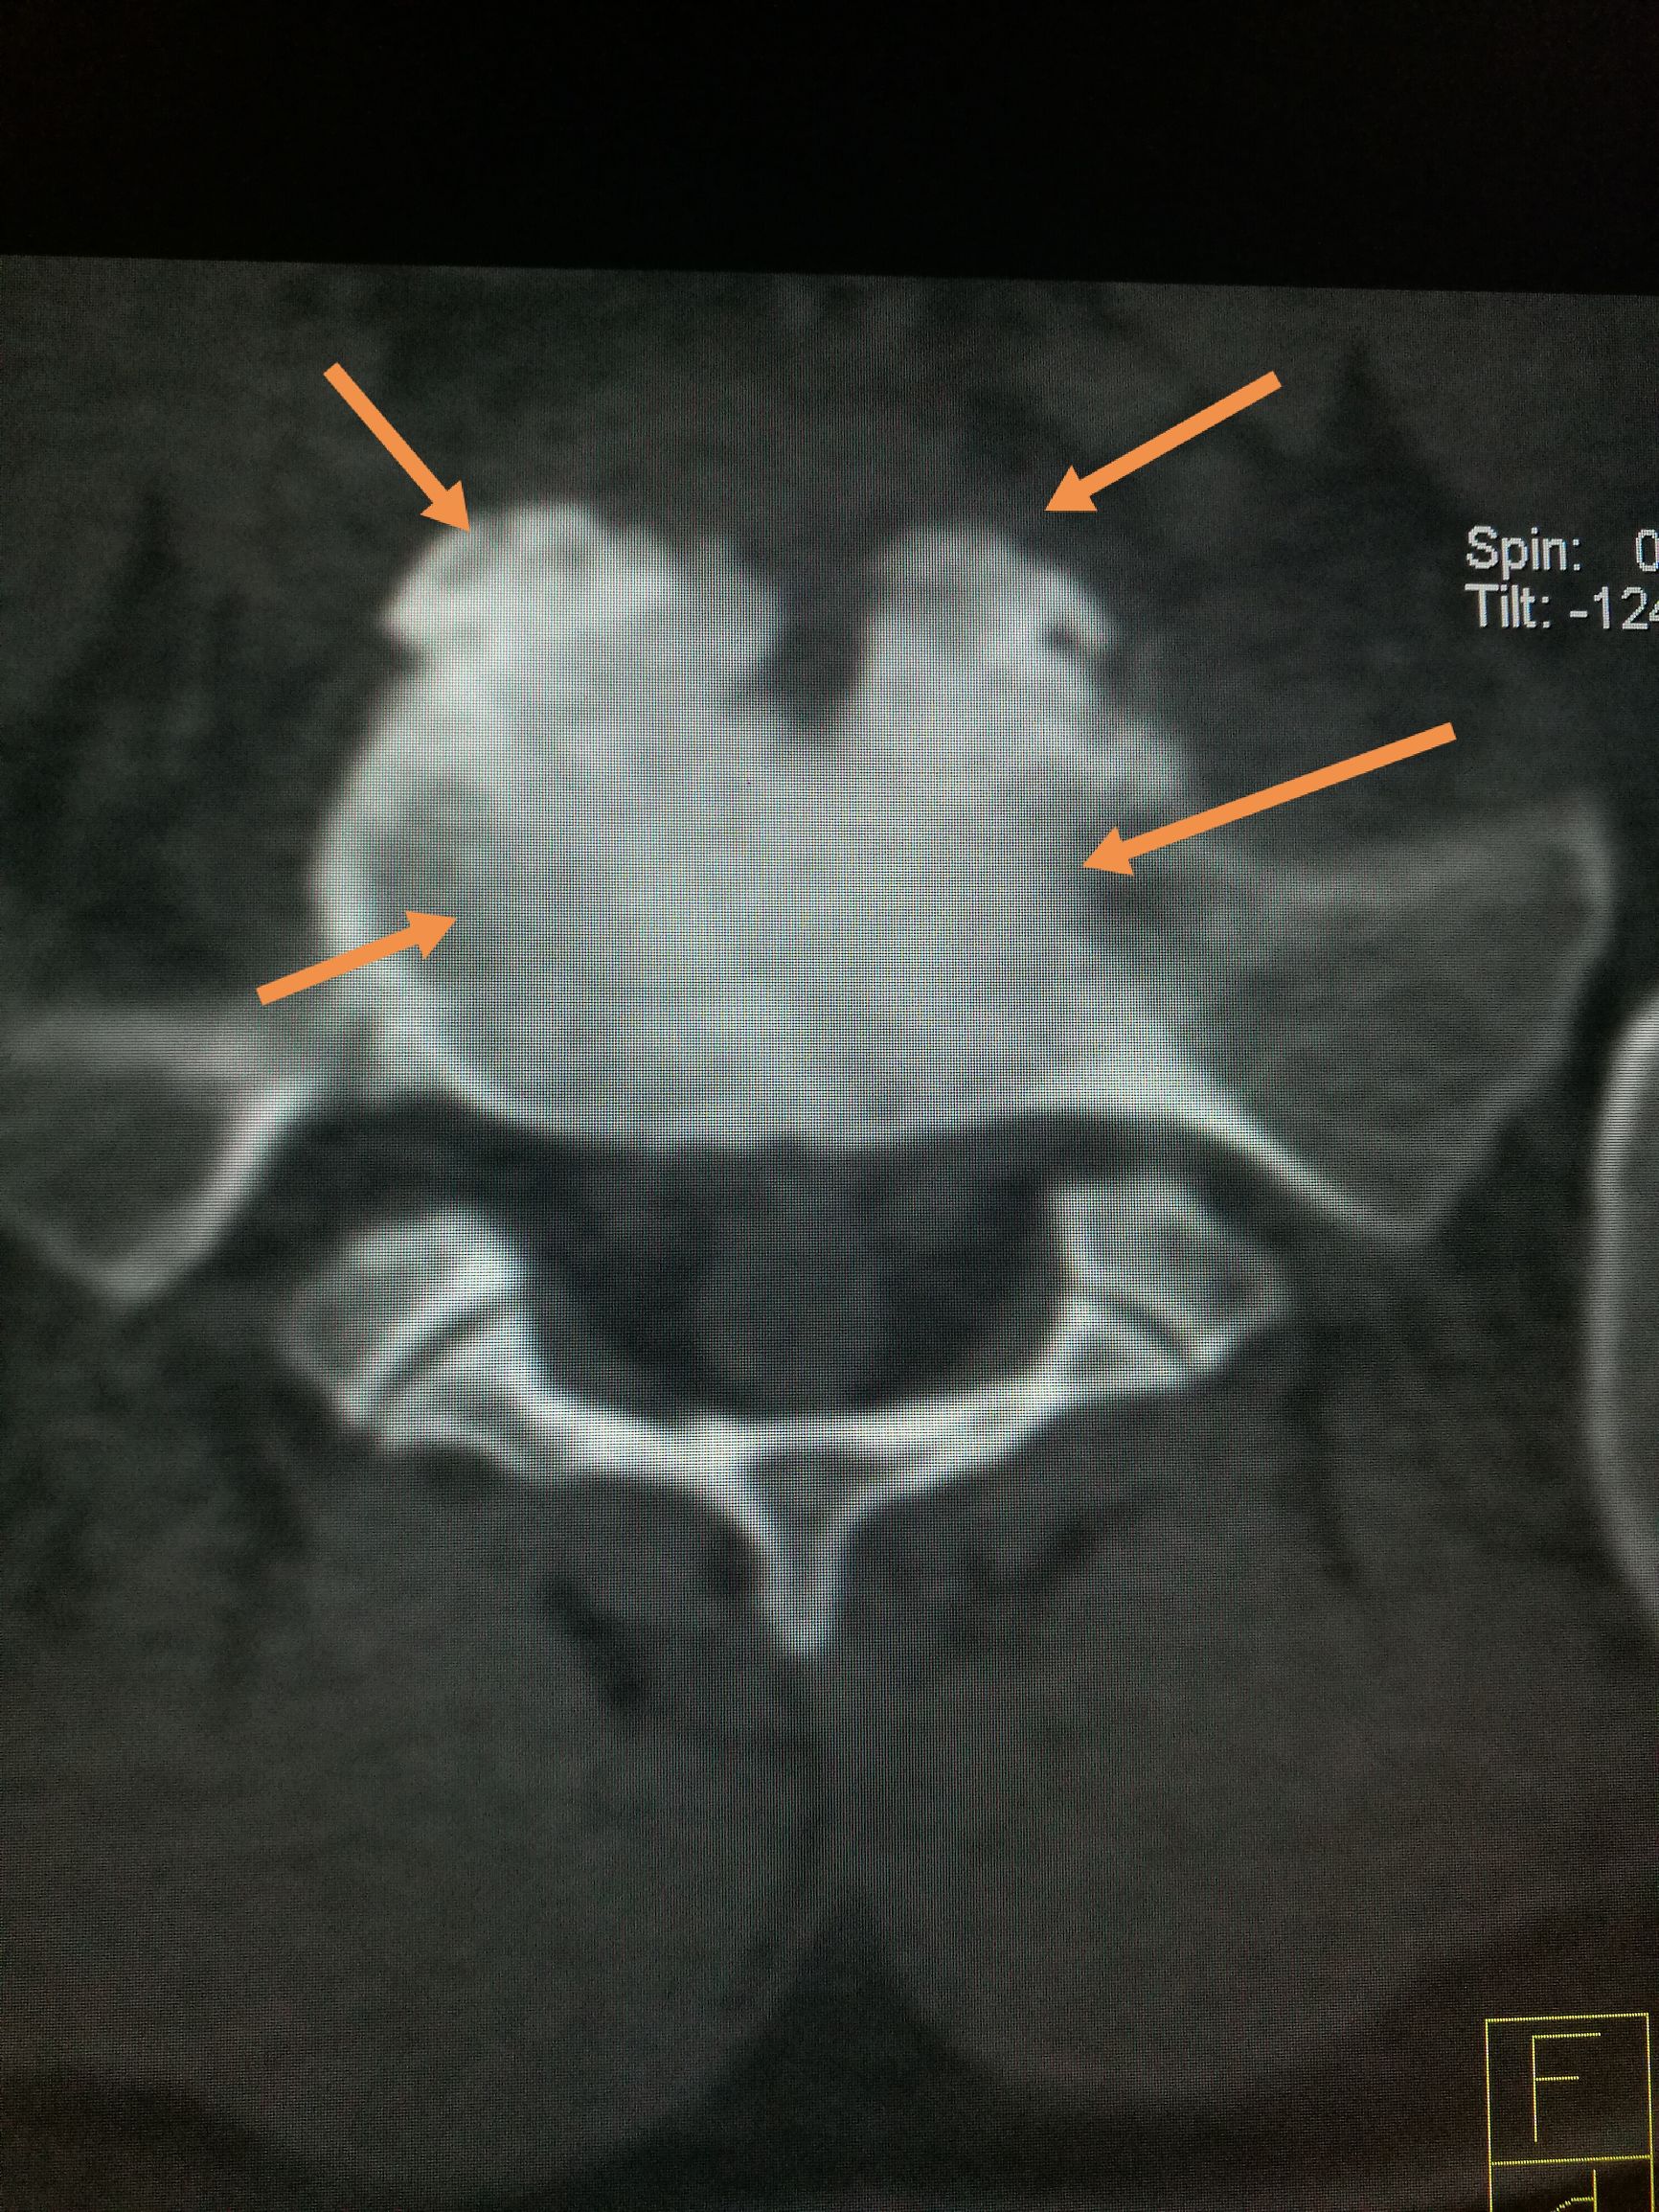

常吃牛羊肉,出现腰背痛,小心☞布鲁氏病 ​​​患者,男,22岁,以腰疼数月前来我处就诊,CT扫描可见第五腰椎下缘,骶椎上缘骨质破坏,骨密度增高,椎间隙未见明显狭窄,椎体旁未见软组织肿胀,未见异常包块,随后追问病史,主诉在*疆新**生活两年,后腰疼,在省防疫站查出来是布鲁氏杆菌感染,今来我处复查。